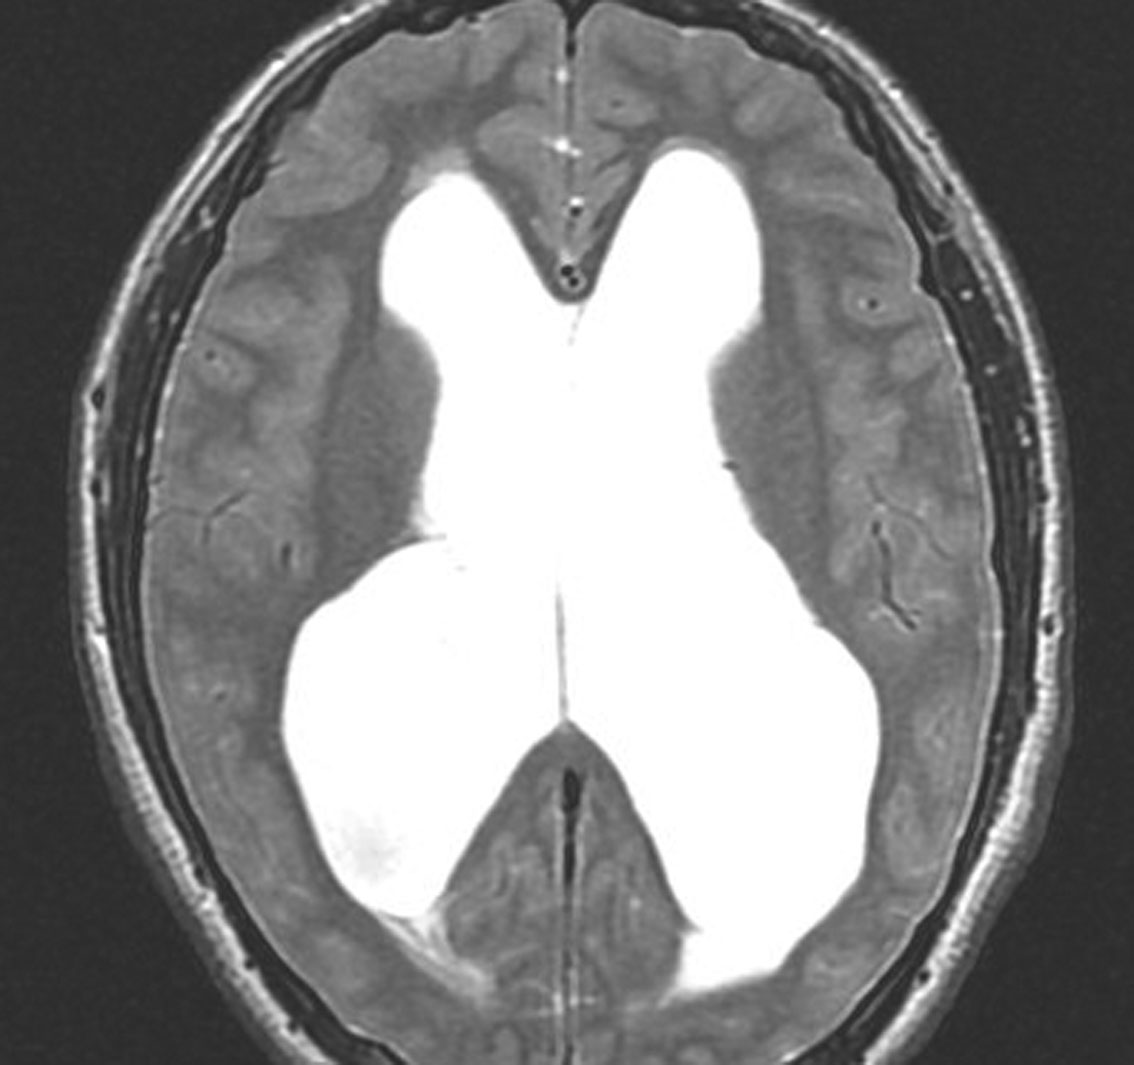

左はT1強調画像,右はFLAIR画像です。中脳視蓋が腫れて腫瘍がにじむように広がっているのがわかります。この腫瘍本体は15歳の時から21歳の時まで大きくなっていないので,中脳視蓋グリオーマ tectal gliomaの診断です。

T1強調ガドリニウム増強画像です。15歳の時は腫瘍の半分以上が強くガドリニウム増強されていましたが,この21歳の時の画像では,中心部やや右寄りに増強像が認められるだけです。この性質は,腫瘍が毛様細胞性星細胞腫であることを示しています。